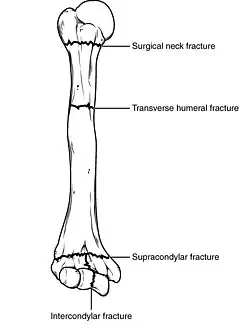

Fractures of the humerus are classified based on the location of the fracture and then by the type of fracture. There are three locations that humerus fractures occur: at the proximal location, which is the top of the humerus near the shoulder, in the middle, which is at the shaft of the humerus, and the distal location, which is the bottom of the humerus near the elbow.[9] Proximal fractures are classified into one of four types of fractures based on the displacement of the greater tubercle, the lesser tubercle, the surgical neck, and the anatomical neck, which are the four parts of the proximal humerus, with fracture displacement being defined as at least one centimeter of separation or an angulation greater than 45 degrees. One-part fractures involve no displacement of any parts of the humerus, two-part fractures have one part displaced relative to the other three; three-part fractures have two displaced fragments, and four-part fractures have all fragments displaced from each other.[13][14][3] Fractures of the humerus shaft are subdivided into transverse fractures, spiral fractures, "butterfly" fractures, which are a combination of transverse and spiral fractures, and pathological fractures, which are fractures caused by medical conditions.[12] Distal fractures are split between supracondylar fractures, which are transverse fractures above the two condyles at the bottom of the humerus, and intercondylar fractures, which involve a T- or Y-shaped fracture that splits the condyles.[7]

Classification